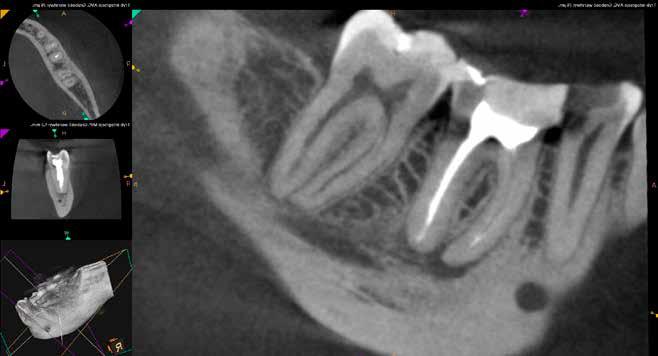

Mind a periapicalis röntgenfelvétel, mind a CBCT-felvétel igazolta, hogy a fragmentum mélyen a gyökércsatorna görbülete mögött, az apikális harmadban helyezkedik el a mesiobuccalis csatornában, valahol a mesiolingualis csatornával történő egyesülés után. Ezenfelül mind a mesialis, mind a distalis gyökércsúcs körül periapicalis gyulladás jelei voltak megfigyelhetőek (1–3. ábra). A betört eszköz nagyjából 5 mm-es hosszúsággal rendelkezett. A mesiolingualis csatornán keresztül a betört fragmentum mellett történő további gyökércsatorna-megmunkálást kockázatosnak ítéltük, mivel nagy esélyt láttunk rá, hogy így a másik eszköz is eltörik, amely pedig a gyökértömés elkészítését nehezítette volna. Azonban a SWEEPS technológiának és a biokerámia sealereknek köszönhetően más megoldási lehetőségek is nyitva álltak előttünk.

ábra: Kiindulási röntgen. A felvételen jól látható a betört eszköz és a periapikális lézió.

2. ábra: Kiindulási CBCT-felvétel. A betört eszköz mélyen a gyökércsatorna görbülete mögött található.

3. ábra: A betört eszköz vége jóval a mesiobuccalis és mesiolinguális csatorna egyesülésének pontja alatt helyezkedik el.